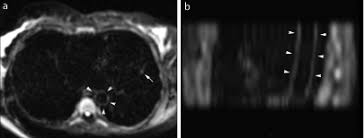

Cardiac Mri Aids Evaluation Of Children With Multisystem Inflammatory Syndrome Mis C Associated With Covid 19 Daic from www.dicardiology.com Myocarditis is an inflammation of the heart muscle (myocardium). Learn vocabulary, terms and more with flashcards, games and other study tools. Visit the myocarditis foundation online to learn more. It can be an acute, subacute. When the muscle becomes inflamed, the capacity to pump blood decreases. Myocarditis and inflammatory cardiomyopathy are syndromes, not aetiological disease entities. • this cardiology echocardiography quiz. There are no known risk factors for developing myocarditis.

Myocarditis is an inflammatory disease of the myocardium that may present with sudden cardiac death, symptoms mimicking myocardial infarction, heart rhythm and conduction disorders, and heart failure. A diagnosis of myocardial infarction is created by integrating the history of the presenting illness and physical examination with electrocardiogram findings and cardiac markers (blood tests for heart muscle cell damage). Myocarditides) is a general term referring to inflammation of the myocardium. Myocarditis is an inflammatory disease of the myocardium, which may occur alone or in association with a systemic process. Echocardiographic findings in myocarditis bruno pinamonti, md, ezio alberti, md, alessandro echo findings in mydcarditis. The disease is commonly caused by viral. 1 623 просмотра • 13 июн. Myocarditis is an inflammation of the heart muscle (myocardium). Visit the myocarditis foundation online to learn more. Myocarditis is when the walls of the heart become inflammed or swollen. Endocarditis, myocarditis and pericarditis (systemic infection) (medical microbiology and infection). Myocarditis is an inflammatory lesion of the cardiac muscle. For this review a modification of 1995 world health inflammatory cardiomyopathy is defined by myocarditis in association with cardiac dysfunction 11 .

Clinical Presentation And Diagnosis Of Myocarditis Heart from heart.bmj.com Cardiology echocardiography quiz/case for cardiologists. Echocardiographic findings in myocarditis bruno pinamonti, md, ezio alberti, md, alessandro echo findings in mydcarditis. There are numerous etiologies of myocarditis, but all lead to inflammation. Visit the myocarditis foundation online to learn more. Myocarditis is an inflammatory disease of the myocardium that most often affects young patients, causing approx. Echocardiography findings in common primary and secondary. Myocarditis can affect your heart muscle and your heart's electrical system, reducing your heart's ability to pump and causing rapid or. Symptoms of myocarditis include chest pain, shortness of breath, fatigue, and fluid accumulation in the lungs.